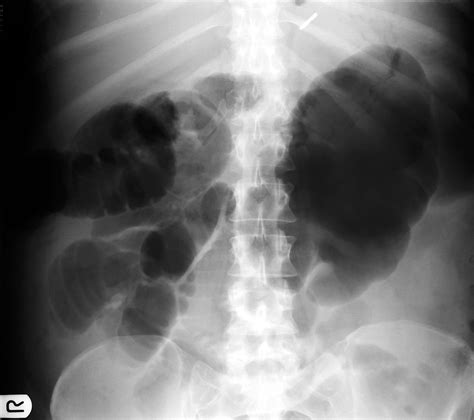

Imaging tests can provide valuable insights into the cause of abdominal distension back pain. Common imaging tests include:

• X-rays: To check for bone fractures or other structural issues.